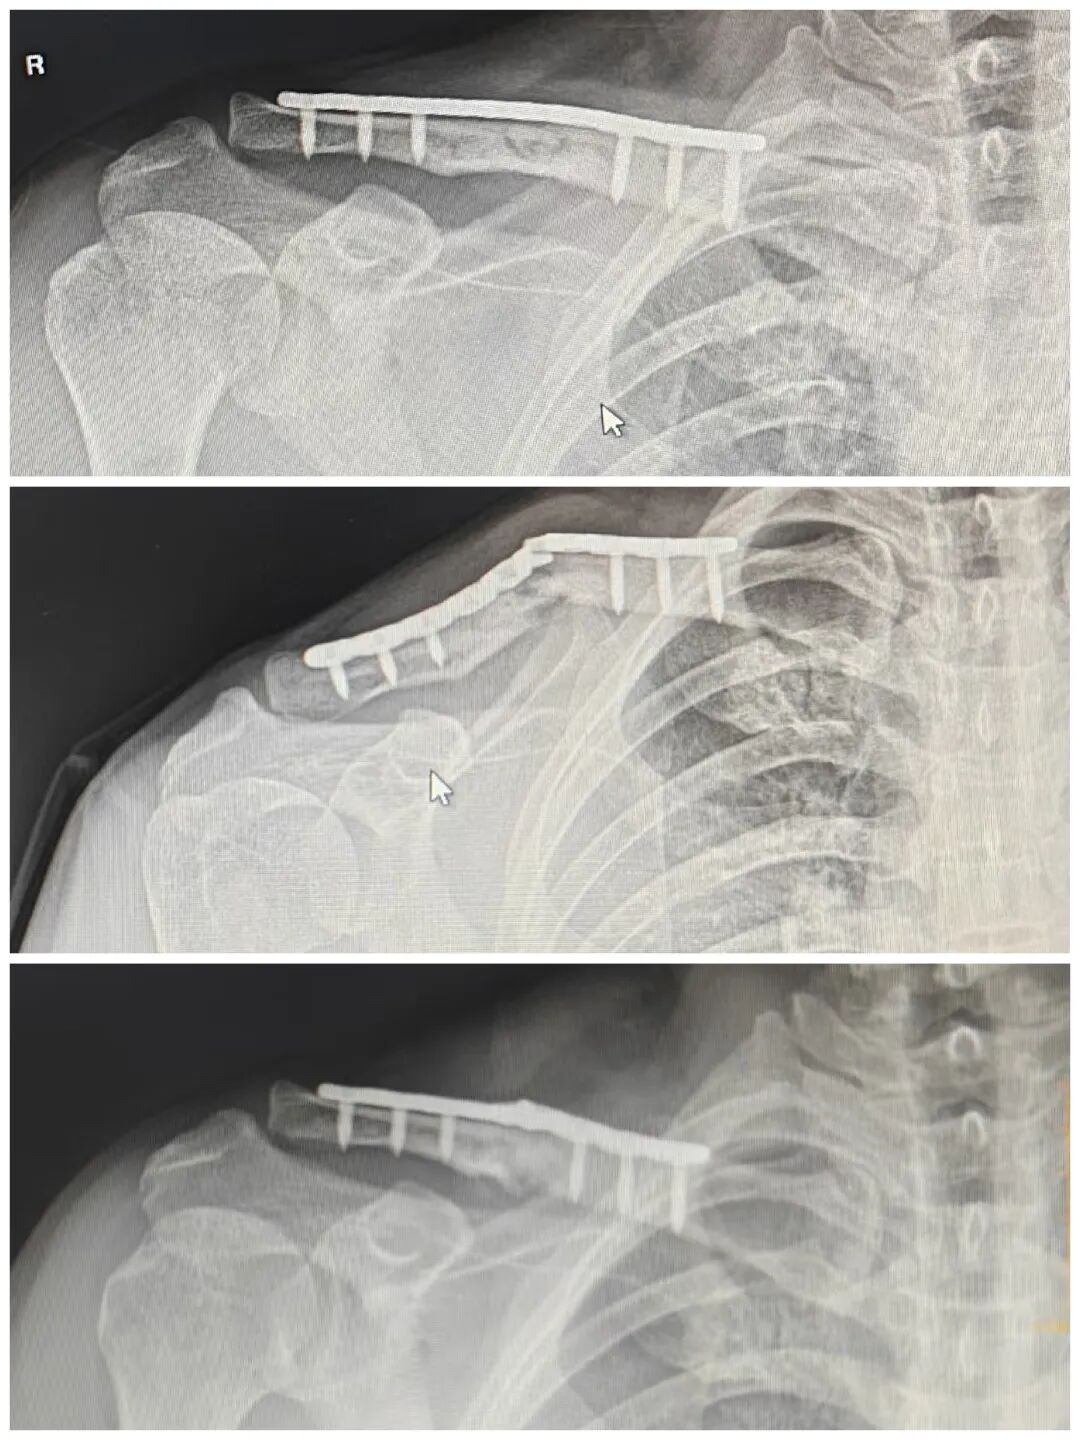

追问病史

骑摩托车摔车,摔断

怎么处理?翻修?

取髂骨植骨?前侧加板?

患者强烈恐惧手术

拒绝再手术

怎么办?

有没有一种非手术治疗?

前臂悬吊,保守吧